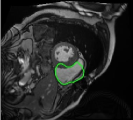

4.3 Comparison with cardic MR images for right ventricle segmentation

Cardiac MRI images often suffer from intensity inhomogeneity due to the varying magnetic susceptibility of cardiac tissues. This can lead to ambiguous boundaries, making it hard for models to consistently identify the left ventricle. Moreover, the heart is composed of several complex anatomical structures, including chambers, valves, and surrounding tissues. Accurately delineating the borders between these various components can be difficult, especially when they are closely positioned or exhibit similar intensity characteristics. In this section, we demonstrate the effectiveness of the RefLSM in segmenting cardiac MR images. The cardiac MR images are standardized to a size of . To enhance the credibility of the proposed model, we segmented 5 cardiac MR images compared the results with 6 other models, including the ALF [MA2019201], LoGRSF [DING2017224], ABC [WENG2021115633], RESLS[8765635], ICTM [WANG2022108794] and FeaACM [XUE2024110673] models. Fig. 5 displays the partial results from all the segmentation models. It is clear that the segmentation results from the RefLSM closely align with the ground truth of the left ventricle segmentation. However, the ALF model demonstrates relatively poor ability to capture the overall structure of the left ventricle; it exhibits limitations with precise boundary detection, particularly in areas of intensity inhomogeneity. Consequently, the evolution curve of the ALF fits into an unstable wave-like result. Suffering from intensity inhomogeneity and surrounding anatomical structures, the LoGRSF model, ABC model and RESLS model all represent over-segmentation and under-segmentation to some extent. Additionally, the results in the 6th column of Fig. 5 show multiple instances where where the ICTM model inaccurately identifies adjacent myocardial tissues as part of the left ventricle due to their similar intensity, leading to false positives. While the FeaACM demonstrates some ability to segment the left ventricle, it is not robust and fails to segment the 5th row of Fig. 5. The 2nd and 3rd rows also include small adjacent excessive regions. In contrast, our proposed model demonstrates marked improvements in accurately capturing the left ventricle’s boundaries. It effectively addresses challenges associated with severe intensity inhomogeneity and noise, resulting in better segmentations. The proposed method appear to maintain better structural integrity in the segmented images, closely aligning with the ground truth.

To quantitatively measure the segmentation results of each model, we compute the Dice and Precision values for left ventricle segmentation. Moreover, we opted for a voilin plot to effectively compare the RefLSM with six other models, as shown in Fig. 7. The results clearly demonstrate that the RefLSM yields superior Dice and Precision values than the other representative models, indicating its closer alignment with the ground truth and highest segmentation accuracy.